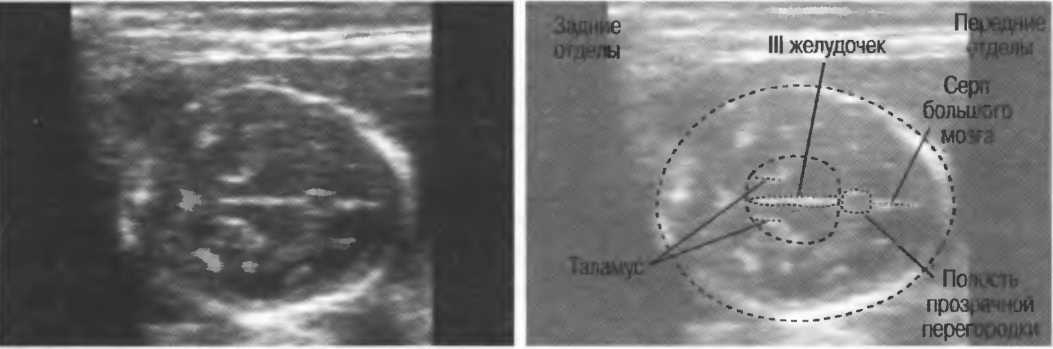

Прозрачная перегородка узи

Прозрачная перегородка узи 109 фотографий